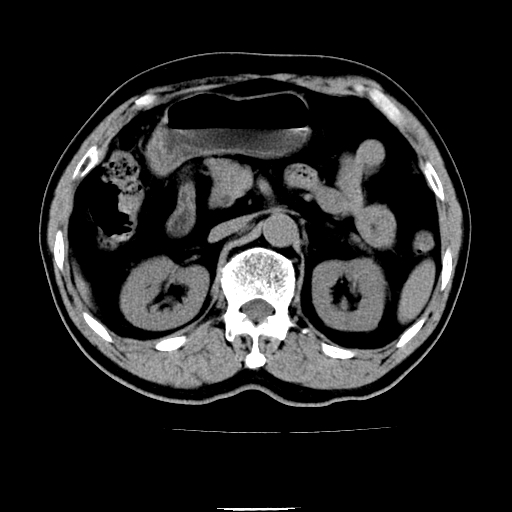

以下是引用chenqiong在2010-3-25 20:56:00的发言:[br]1、胆囊炎,胆囊息肉[br]2、肝内胆管及胆总管扩张,胆总管下端结石[br]3、十二指肠乳头旁憩室

以下是引用zxl51642在2010-3-26 10:47:00的发言:[br]胆囊炎,胆囊息肉,胆总管扩张,但未看到明显肿块,肝内胆管扩张不像恶性,炎性狭窄或阴性结石可能吧,建议mrcp,右肾小囊肿